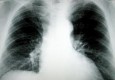

Povodom Hrvatskog dana bez duhanskog dima zagrebački Gradski ured za zdravstvo i Poliklinika za bolesti dišnog sustava pozivaju pušače i bivše pušače na na besplatan pulmološki pregled. Akcija besplatnih pregleda za pušače i bivše pušače starijih…